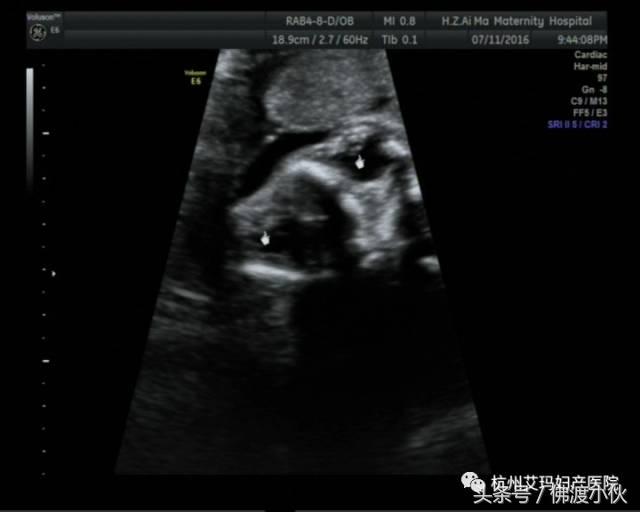

病例二:

胎儿双侧晶状体回声透声差,浑浊,考虑双眼先天性白内障(见下图)。